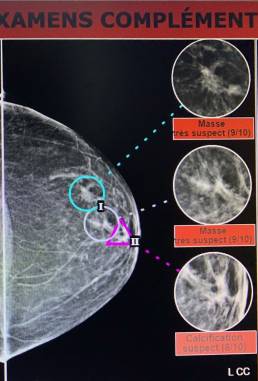

80-year-old female, left breast tumor. A first radiologist found nothing in mammo and breast echo, MammoScreen® positive for the increased left nipple retro opacity. A breast MRI was performed and a second look ultrasound was performed with micro biopsy: lobular carcinoma infiltrating RH +

*Case from Dr. Le Van An